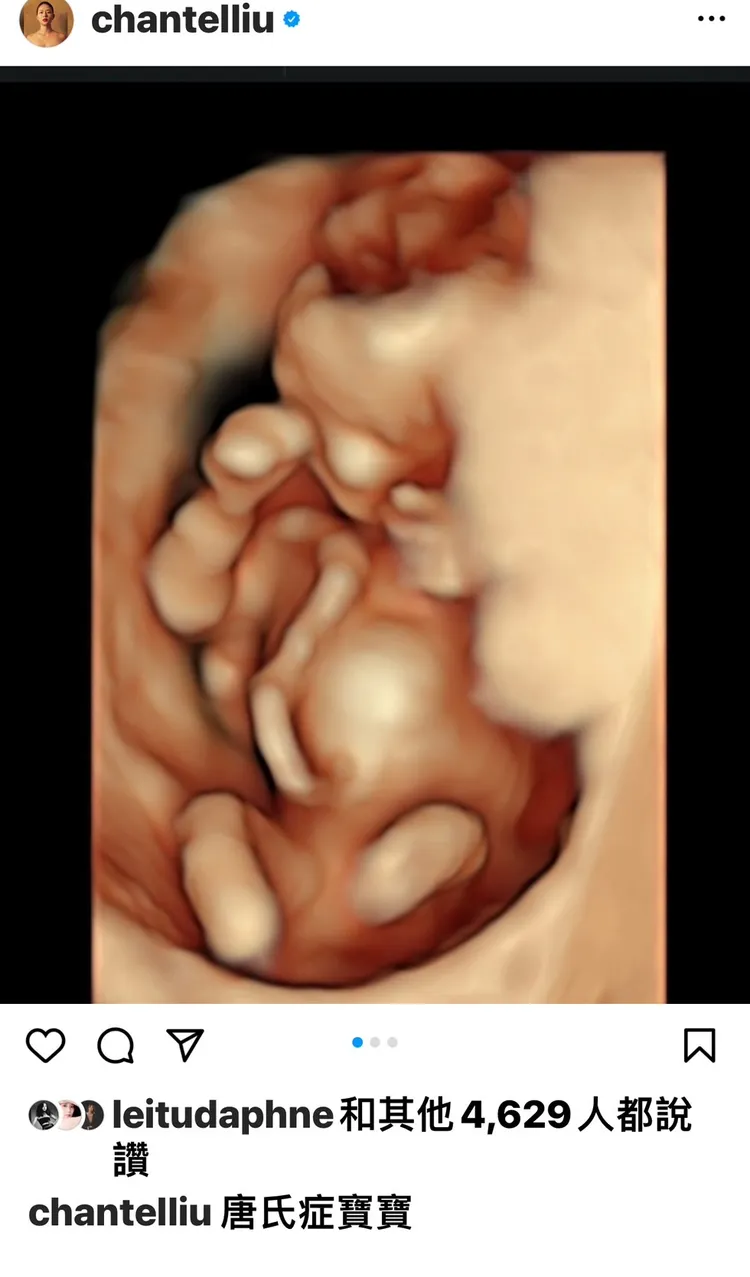

劉香慈標題「唐氏症寶寶」。翻攝劉香慈臉書

日前她發文,由於配圖是高階超音波照,加上標題是「唐氏症寶寶」,讓不少人擔心她是否貝比有情況。對此劉香慈說:「我除了健保產檢,診所安排的自費產檢項目一次都沒有少,抽血、尿液、超音波檢查目前也都是正常。」

她接著表示:「其實那篇文章主要是想要表達,我很感激觀世音菩薩讓我的孩子到目前為止都是平安健康、正常發展。每次產檢我都不在乎是否可愛、長腿、挺鼻、長得像誰,只要醫生說發展一切正常我就心滿意足,可以鬆了一口氣、用輕盈的步伐走出診間。醫生也會檢查心臟、心室、血流有沒有問題,胎兒有無腹裂而臟器外露。」

其實主要是在40歲這年懷了第3胎,難免想很多,感觸良多,她說:「醫生在說沒問題之前,我躺在那都還是會懸著一顆心、壓力指數上升;經歷3胎的歷程,讓我有感而發:感恩我的孩子目前一切健康,也同時觸發我思考,萬一我的孩子是不健康、基因有缺陷,我會做出什麼樣的選擇。我也看過身邊朋友在胎兒確定不健康的時候,經歷痛苦,以淚洗面最後勇敢做出決定。因此我的選擇也是我在近10年來內心反覆的自我辯證而得到屬於我自己的答案。」